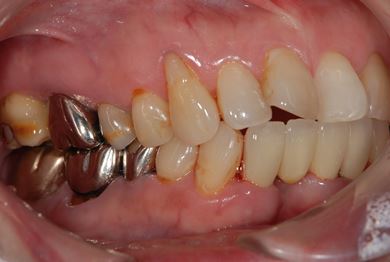

| 性別/年齢 | 女性 / 55歳 | ||||||||||||||||||||||||||||||||

| 主訴 | 20年程前に矯正のため義歯にしたものの具合が悪いので、いいものにかえて欲しい。歯ぐきから骨が見えてきたところがあるので、治療して欲しい。 | ||||||||||||||||||||||||||||||||

| 治療方針 | 保存不能な歯を抜歯し、セラミック治療にて、機能的・審美的回復を行う。 | ||||||||||||||||||||||||||||||||

| 治療内容 | ジルコニアオールセラミッククラウン4本(オールセラミック用土台3本) | ||||||||||||||||||||||||||||||||